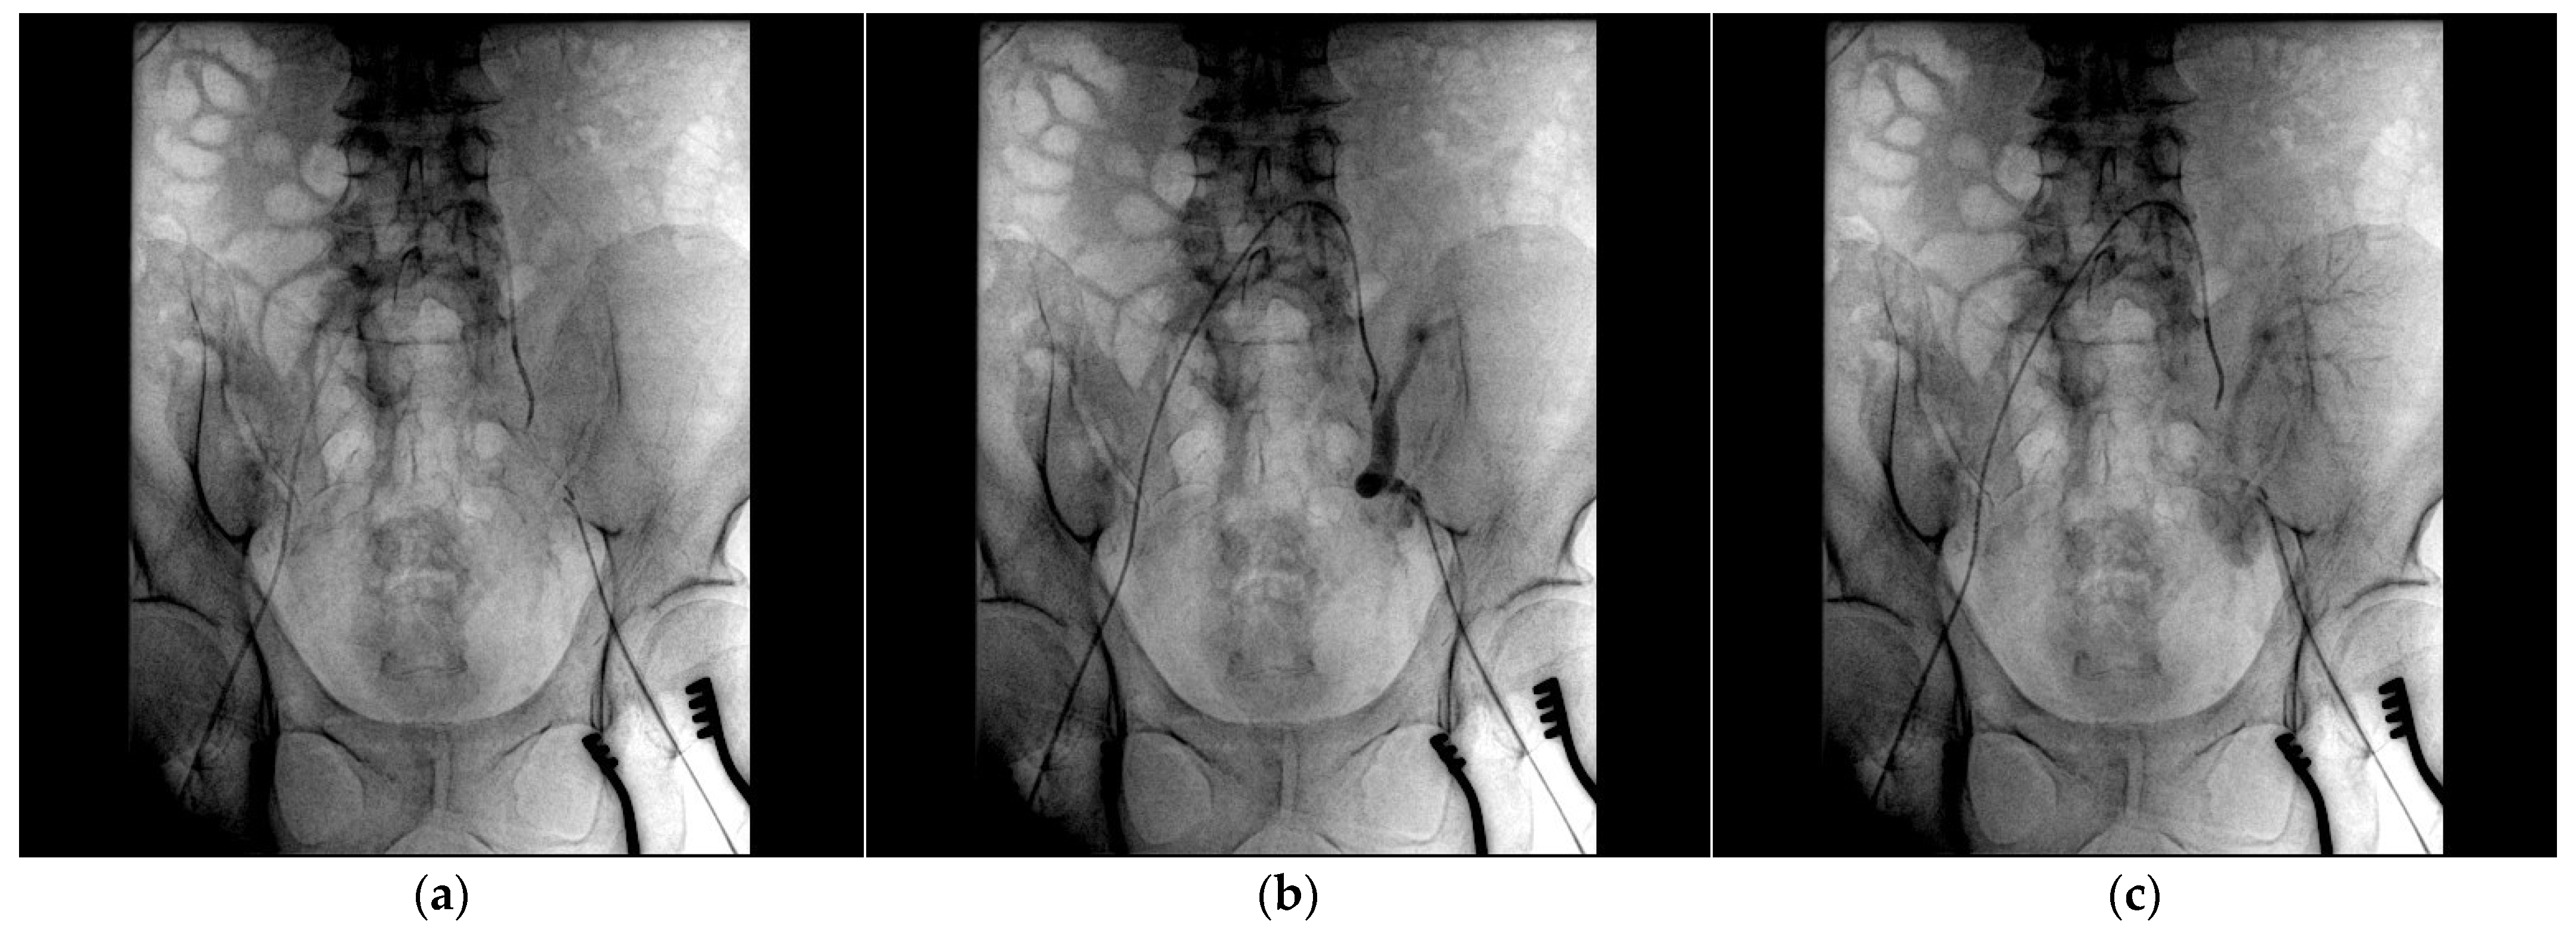

- Bypass grafting ensured continuous perfusion to the lower limb, mitigating the risk of ischemic complications;

- Endovascular stenting minimized surgical trauma while effectively excluding the pseudoaneurysm;

- Coil embolization provided an additional layer of pseudoaneurysm isolation, further enhancing treatment efficacy.